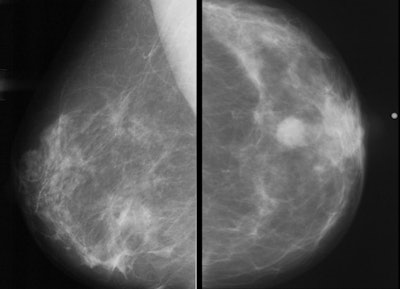

Women who are screened for breast cancer every two years have more advanced cancers -- as well as more cancers between screening rounds -- than those who are screened annually, according to a study to be presented next week at RSNA 2019 in Chicago. Those treated biennially also generally require more aggressive treatment.

Researchers scoured a breast imaging database at a U.S. National Cancer Institute designated cancer center and found breast cancer in more than 200 women. Most women underwent annual screening, while a smaller proportion screened biennially. The biennial group fared worse in terms of later-stage cancers, interval cancers, larger tumor sizes, and more aggressive treatment.

She and her colleagues sought to weigh in by comparing breast cancer tumor characteristics and treatment regimens among women undergoing annual mammography versus those getting biennial screenings in the years 2016 and 2017 at the cancer institute. The study group included 232 women, ages 40 to 84, who were diagnosed with breast cancer. The two groups had no significant differences in baseline characteristics such as age, menopausal status, hormone replacement use, family history, and race.

The vast majority (86%) underwent annual screening, defined as once every nine to 15 months, while the remaining 32 had biennial screening, or once every 21 to 27 months. The mean age at cancer diagnosis among was 62. Almost three-quarters of the cancers were invasive. Other statistics are below.

Late-stage cancers | 43.8% | 24% |

Interval cancers | 38% | 10.5% |

Median tumor size | 1.2 cm | 1.1 cm |

The study also found women who had biennial screening tended to have more aggressive treatment, such as chemotherapy and dissection of the axillary lymph nodes, where cancer from the breast often spreads.

"There were trends toward less frequent axillary lymph node dissection and less frequent use of chemotherapy with annual screening compared with biennial screening," Moorman said.